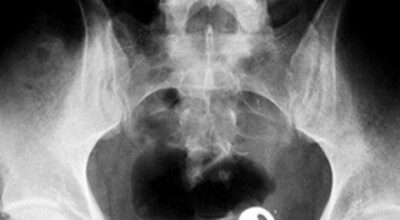

Esta recopilación de imágenes recoge alguna de las situaciones más estrambóticas que se han podido dar en una sala de rayos X. Todas ellas tienen algo en común: Son objetos extraños para el cuerpo humano que, de alguna manera han encontrado una vía de entrada, pero se han perdido a la hora de encontrar la de salida.

Muñecas de juguete descabezadas, botellas, armas, frascos, botes de plástico, teléfonos y hasta una cinta de casete pueden encontrarse en esa suerte de “punto limpio” al que ha quedado reducido el interior de los afectados.